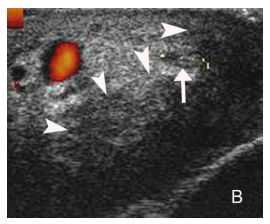

Во время УЗИ икроножный нерв был виден вблизи малой подкожной вены ( v . saphena parva ) с варьируемой позицией относительно нее, и продолжался до латеральной лодыжки голеностопного сустава. Во время УЗИ, икроножный нерв был определен как структура толщиной 1,5 мм. Нерв обладал типическими ультразвуковыми качествами периферического нерва. В поперечной плоскости наблюдалась овоидная структура, состоящая из маленьких гипоэхогенных вкраплений с гиперэхогенными областями (по типу «медовых сот»). В продольной плоскости можно было наблюдать фибриллярную структуру, состоящую из параллельных гиперэхогенных линий, окружающих гипоэхогенные трубчатые нервные пучки.

Чаще всего, наблюдалось гипоэхогенное утолщение (8/10 случаи) нерва. Гиперэхогенное утолщение наблюдалась у двух пациентов с укусами клещей. У одного пациента потвердели Болезнь Лайма, его нерв был утолщен на протяжении 10 см на месте хронической мигрирующей эритемы ( erythema migrans chronicum ) (Рис. 3). Это открытие до нашей публикации не было описанное в литературе.